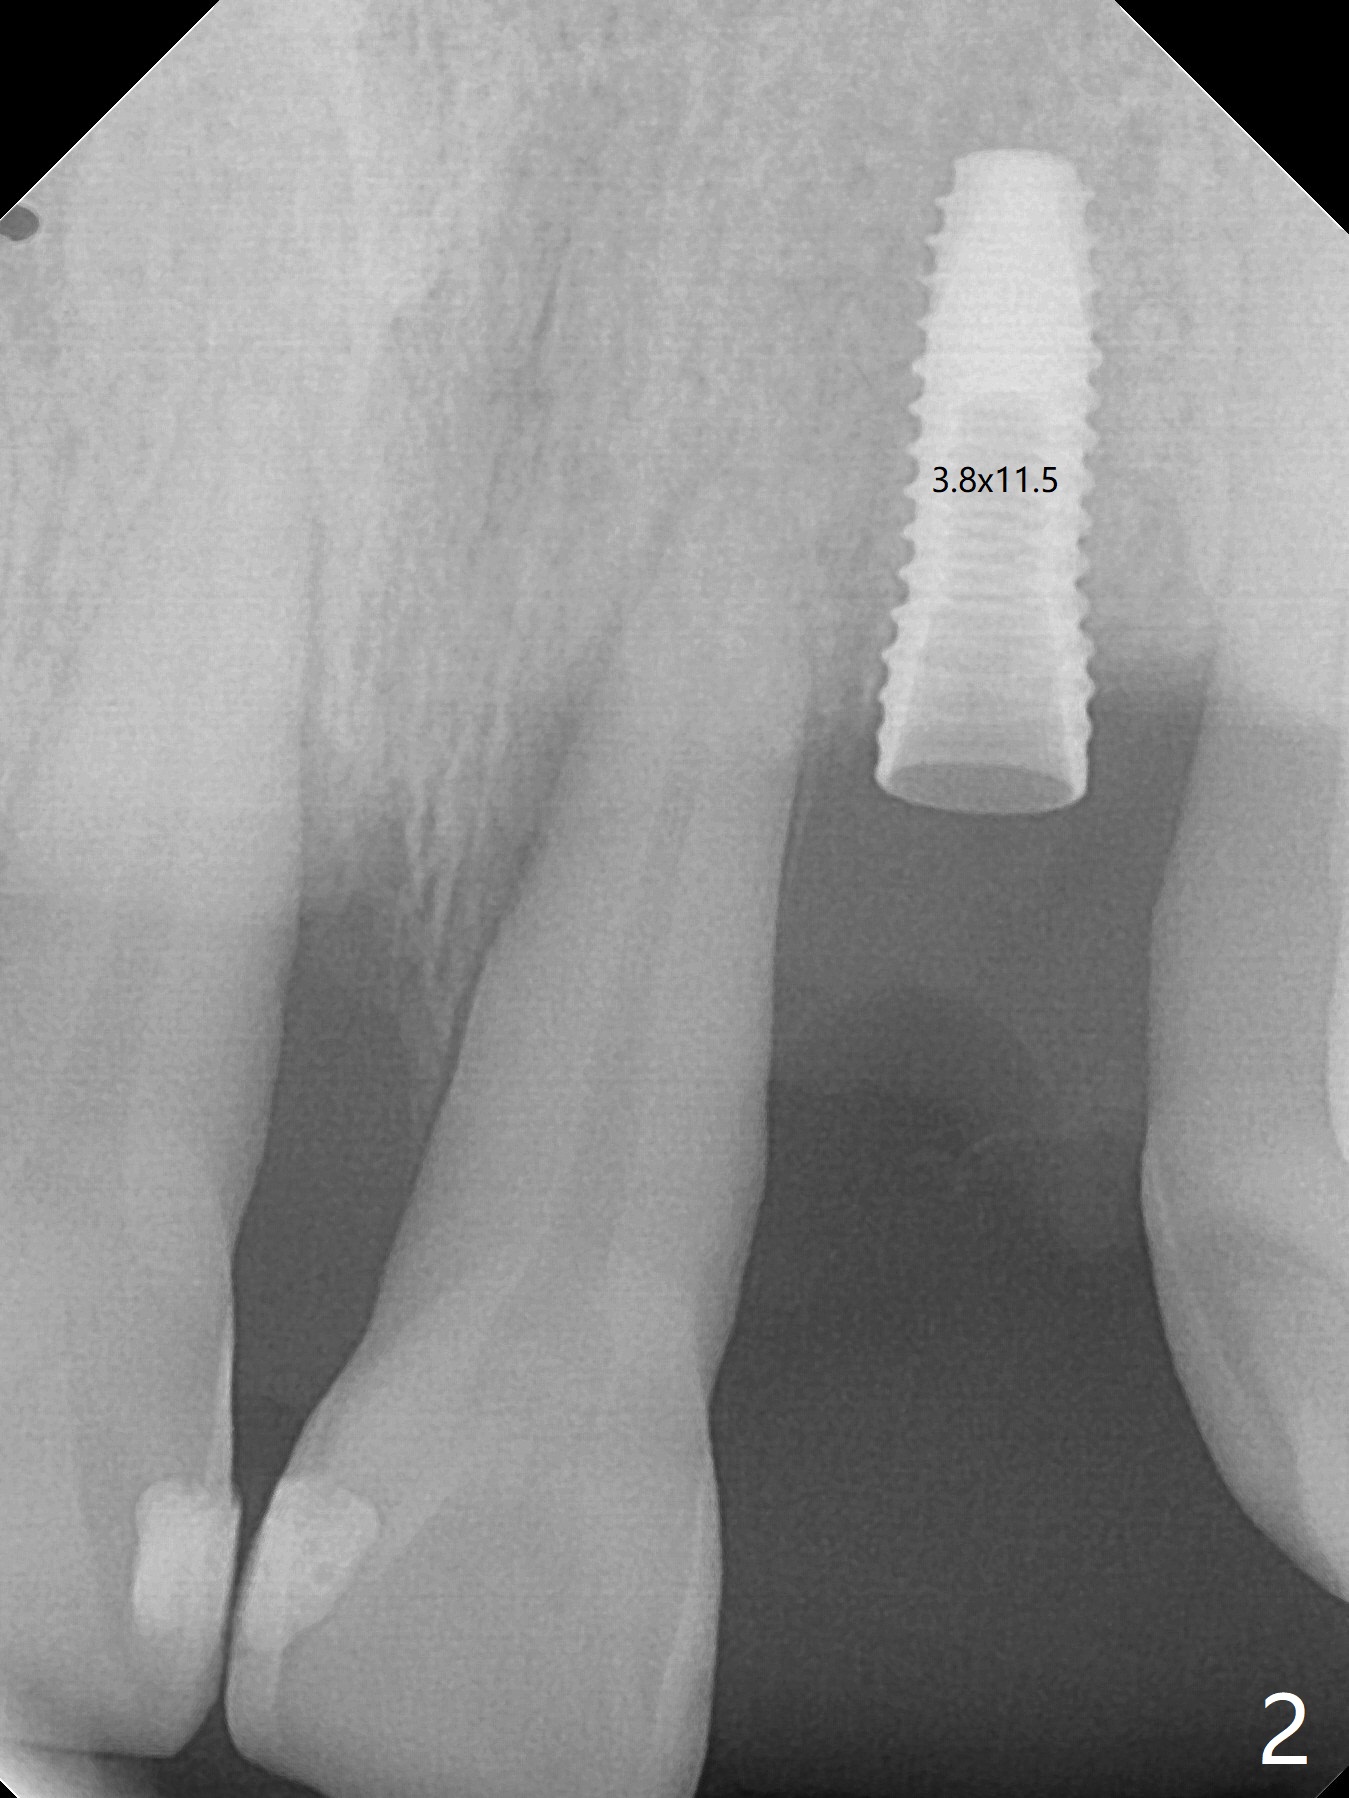

实验结果表明红管抽取上清液形成粘性骨块比白管快。左上二拔除,即刻徒手钻洞(图一),初步植入3.8x11.5毫米植体(图二),调整植体深度,然后放置直径4.5毫米长基台(图三,DIO UF; 牙龈厚度大于6毫米),最后填入大量粘性骨粉(图四,五 *),植体颊侧近中骨粉不足(图五 ^),之后再次充填骨粉。制作即刻修复物,颊侧瘘道和牙槽窝开口放置PRF膜。术后三周临时牙冠松动,取出后者,颊侧空间有两个区域:牙龈和骨粉(图六:白,黑星号)。由于脑部手术,术后接近一年病人回来取模。由于基台长,临时牙冠还没有脱落(图八)。牙龈袖正常(图九:*)。术后一年骨粉仍在植体,基台交界处(图十)。